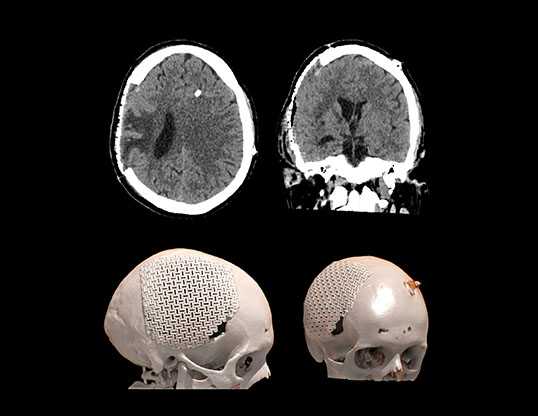

Визуализируется обширная инвагинация кожного лоскута в полость дефекта, смещение срединных структур влево, сдавление САП правого полушария и сглаженность борозд. Причиной данного состояния явилась гиперфункция шунта.

Данному пациенту была произведена краниопластика дефекта черепа, коррекция программируемого клапана давления. Пациент выписан на третьи сутки в удовлетворительном состоянии с полным регрессом неврологической симптоматики.